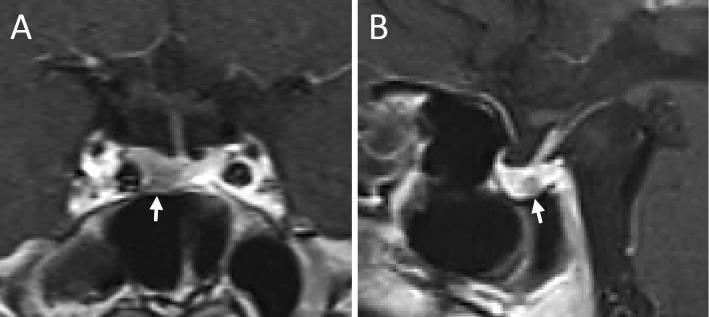

A 39-year-old woman with a 3-year history of a rounded face developed widespread myalgia. Detailed examinations revealed no disorders that could explain the pain other than concomitant Cushing's disease and central hypothyroidism. Both the hypercortisolemia and hypothyroidism completely resolved after the patient underwent surgery to treat Cushing's disease, but she continued to experience unresolved myalgia and met the diagnostic criteria for fibromyalgia. Few studies have so far investigated patients with fibromyalgia associated with Cushing's syndrome. In our case, the hypothyroidism caused by Cushing's disease probably played an important role in triggering and exacerbating fibromyalgia. This highlights the need to examine the endocrine function in patients with muscle pain.

https://cdn.ncbi.nlm.nih.gov/pmc/blobs/772d/5140872/a42cee2c21f1/1349-7235-55-3185-g001.jpg